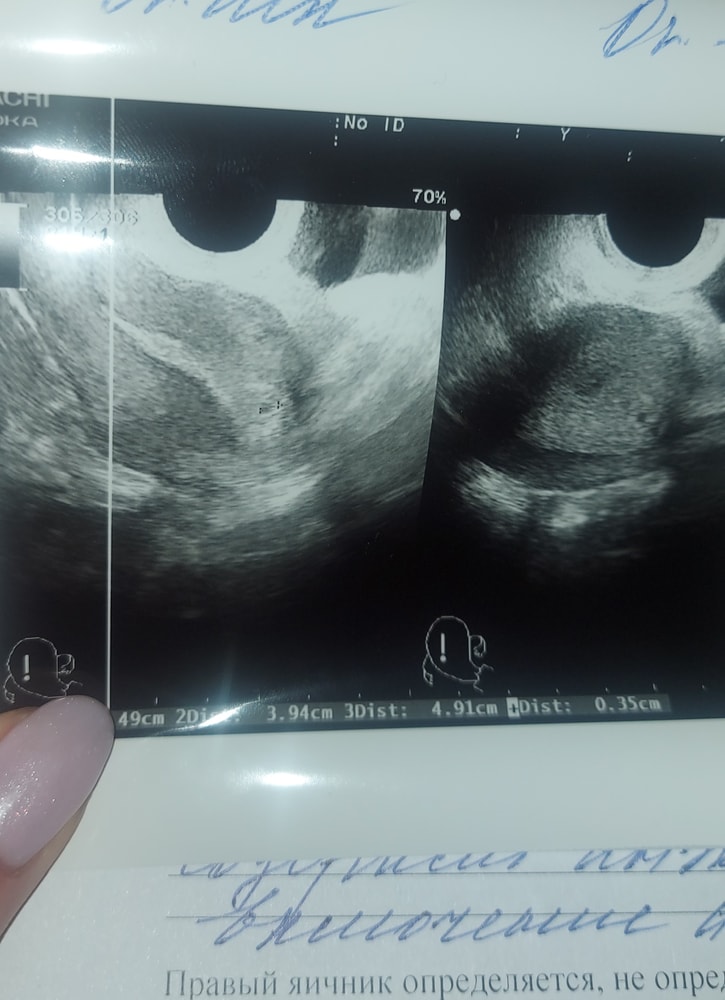

И это на 6й день задержки. Больше ничего сдавать не буду, пить препараты для поддержки тоже, просто жду, когда все разрешится. Ни на что повлиять невозможно все равно. Была вчера на узи, нашли ПЯ 3мм и кисту желтого тела, которая очень болит, что соответствует 3 неделям беременности. сказали прийти через 2 недели. И я читала, что ПЯ видно от 1000хгч, но у меня увидели на 400-500. Не кровит, не болит, только грудь болючая. Пост оставлю на память.